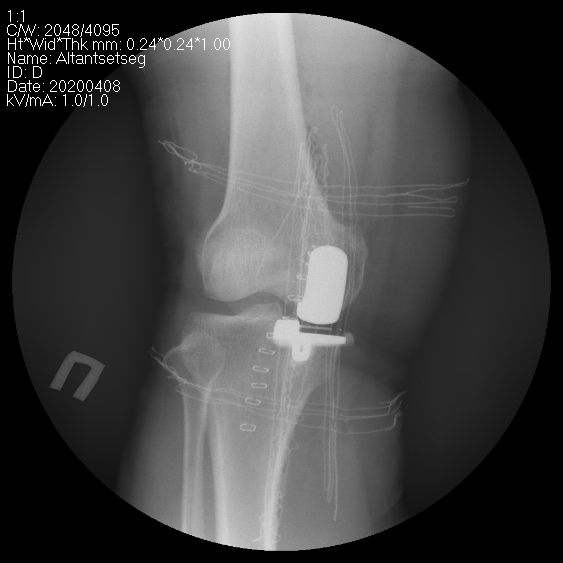

Өвдөгний үе хагас солих мэс засал (UKA) image1

Зураг. Өвдөгний үе бүтэн болон дотор булууг хэсэгчлэн солих мэс засал.